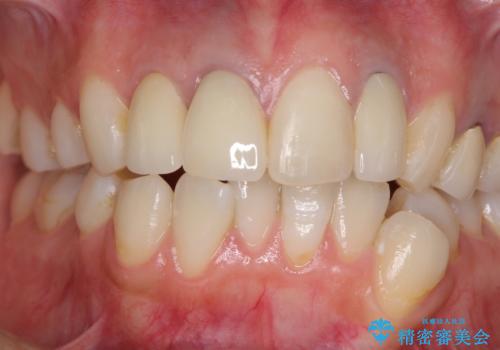

必要な歯には根管治療を行い、金属を使わない土台を植立した上で、オールセラミッククラウンにて補綴することとしました。

色調を統一するために、未治療の1歯もクラウンを装着するかどうか悩んでいらっしゃいましたが、結果としては治療せずに4前歯の色調を合わせることができました。

歯肉の黒ずみも多少改善させることができ、患者様には大変満足していただきました。